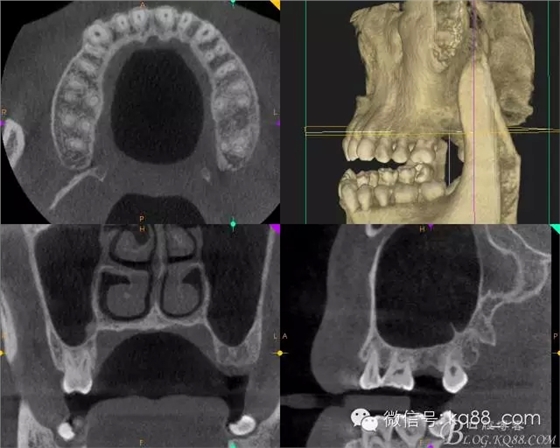

術前拍攝CT發(fā)現(xiàn)該處牙槽骨高度不足需要進行內提升手術,但是 CT上看骨的寬度很好,所以決定采用微創(chuàng)植入。

術前的CT影像